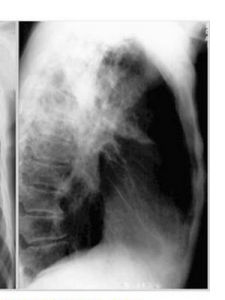

4、慢性纖維空洞型肺結核(Ⅳ型):反覆出現發熱、咳嗽、咯血、胸痛、盜汗、食慾減退等,胸廓變形,病側胸廓下陷,肋間隙變窄,呼吸運動受限,氣管向患側移位,呼吸減弱。血常規檢查可見血沉值增快,痰結核菌培養為陽性,X線顯示空洞、纖維化、支氣管播散三大特徵。